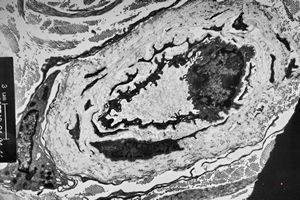

stabbed hypostom of the tick … toluidine-stained semithin section

stabbed hypostom of the tick … toluidine-stained semithin section (montage)